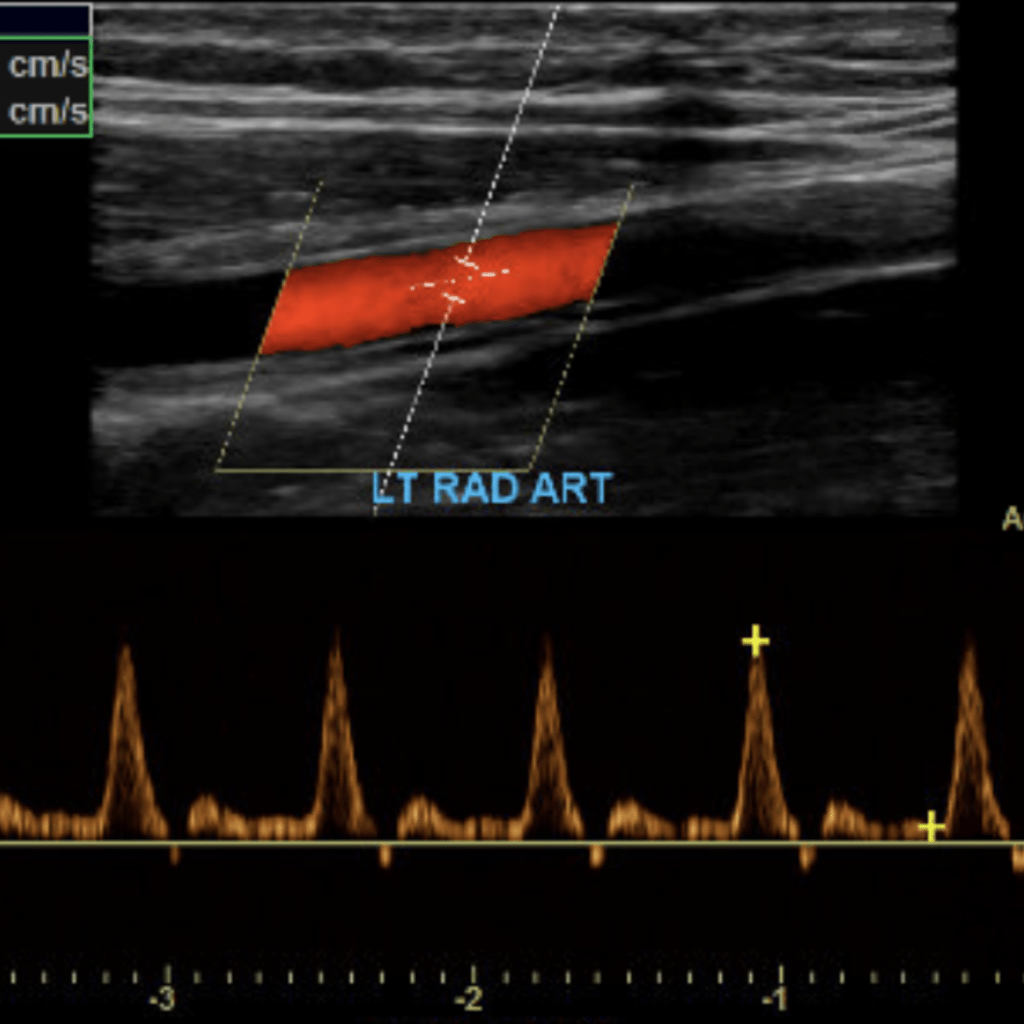

The subclavian artery arises from the brachiocephalic artery on the right and off of the aortic arch on the left. This artery further divides into the axillary, brachial, radial, ulnar, palmar and digital arteries respectively.

Duplex sonography of the extremities is a non-invasive and valuable tool in detecting diseases in the blood vessels of the arms and legs. This post will cover the basic evaluation of the upper and lower extremity arterial systems.